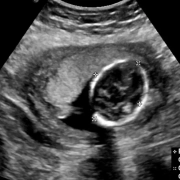

Higher nuchal translucency in ultrasound tied to increased chromosomal anomalies risk: JAMA

A recent study from Ontario, Canada, unveiled a strong link between the measurements of fetal nuchal translucency and the risk of chromosomal anomalies, including conditions less frequently screened for in current prenatal practices. The findings were published in the recent edition of Journal of American Medical Association.

The study involved a massive group of over 414,000 singleton pregnancies, that illuminated the significance of nuchal translucency measurements as an early indicator of genetic conditions by prompting a reevaluation of existing cutoff points for follow-up testing. Nuchal translucency (NT) measurement with ultrasonography is a common in prenatal screening that primarily targets trisomies 21 (Down syndrome) and 18. Traditionally, a cutoff of 3.5 mm or more was utilized to flag pregnancies for further investigation, like the cell-free DNA (cfDNA) screening or more detailed cytogenetic analysis. However, the findings of this study suggest that risks related with chromosomal anomalies may be significantly elevated even at NT measurements below the conventional 3.5 mm threshold.

This study utilized data from the Better Outcomes Registry & Network, Ontario’s perinatal registry and spanned singleton pregnancies with estimated delivery dates from September 1, 2016 to March 31, 2021. The analysis revealed a risk, where increased NT measurements even that were less than 3.5 mm were linked with a increased likelihood of chromosomal anomalies beyond the most commonly screened conditions, such as trisomies 13, 18, 21 and sex chromosome abnormalities.

The study showed an adjusted risk ratio (ARR) of chromosomal anomalies at an alarming 20.33, with an adjusted risk difference (ARD) of 9.94% for the pregnancies with NT measurements between 3.0 and less than 3.5 mm. Also, when the analysis was restricted to less common chromosomal anomalies, the ARR was at 4.97 and the ARD was at 1.40% that underscored a significant increase in risk even for anomalies not routinely included in prenatal screening programs.

These findings were analyzed between March and August 2023 that challenged the adequacy of the current 3.5 mm NT cutoff and also illuminate the need for a precise approach to prenatal screening. The pregnancies with NT measurements less than 2.0 mm showed the lowest risk that indicated lower NT measurements could serve as a reassuring indicator for expecting parents and healthcare providers.